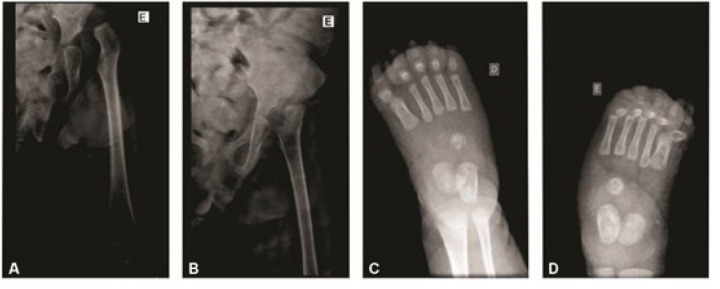

Case description: Two female patients, one aged three years and six months and one aged five months, receiving care from an APAE (Association of Parents and Friends of People with Disabilities) unit, were diagnosed with hyperekplexia 1, a neurological disorder characterized by an excessive startle response. Hyperekplexia cases can be divided into three subgroups: hereditary, sporadic, and symptomatic. Several specialists have examined patient 1 since she was three weeks old, leading to two initial diagnostic hypotheses (childhood chronic non-progressive encephalopathy and spastic cerebral palsy). She was diagnosed with hyperekplexia 1 at eleven months when a genetic test revealed changes in the GLRA1 gene. Patient 2, at birth, presented hyperextension of both legs, low-set ears, cranial asymmetry, prominent occiput, and tremors in the lower limbs. After several tests and evaluations, the final diagnosis was confirmed at three months old. Her family history indicates the possibility of hereditary hyperekplexia.

Comments: The cases were compared with information obtained through a bibliographical review. Both patients presented several symptoms associated with hyperekplexia, including neurological symptoms such as increased startle response, convulsions, and hypertonia, which were alleviated with appropriate treatment. So far, combining multidisciplinary assistance with drug treatment, particularly anxiolytics and anticonvulsants, with clonazepam being the most used, has significantly contributed to both patients' improved quality of life. However, physical symptoms, such as hip dislocation and clubfoot, require future surgical intervention.